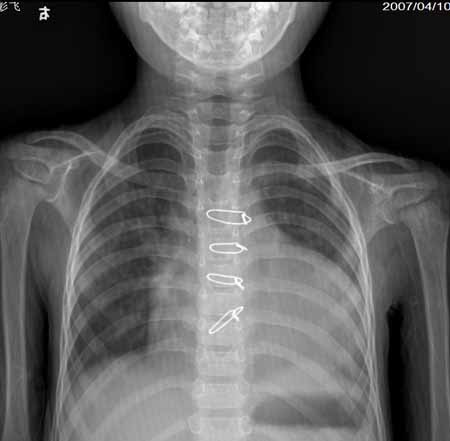

结果收到,大家都没有猜对,法四学习了!肺内出现粗乱血管影或中下肺野及肺门附近有网状血管纹理,为体动脉侧支循环的表现,提示中度肺动脉狭窄。